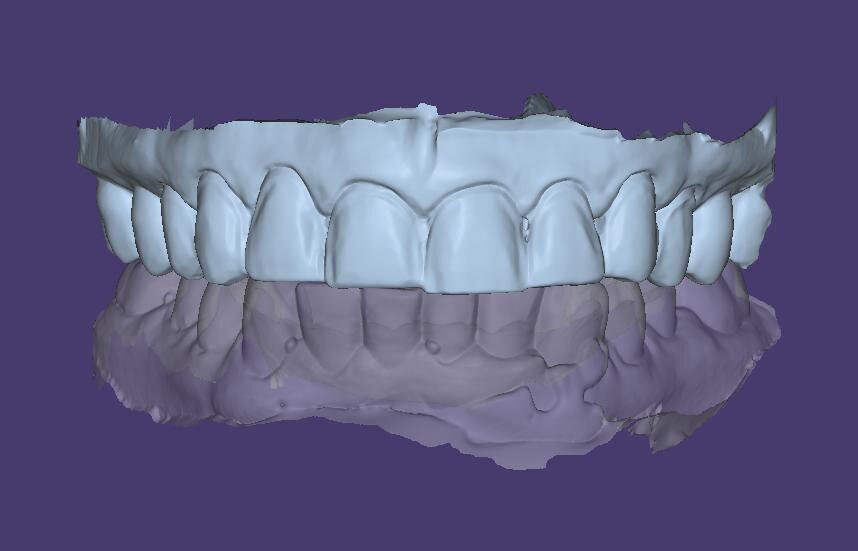

Fig. 14: 3D smile design simulation.

With the diagnostic information acquired during the first appointment, the steps of aligning the models using the face-bow transfer technique with the DFA system were followed. A 2D image of the patient was imported and aligned using match points to develop a 3D functional virtual wax-up by adding restorative material to the maxillary anterior teeth and first premolars. A natural tooth library with square shaped teeth similar to the patient’s natural anatomy was selected to create the virtual diagnostic wax-up to reproduce shape and texture. The dental software used in this case (exocad) also has a tooth colour selection option to show a simulation of tooth shade, which facilitates the patient’s visual perception of the proposed treatment and improves treatment acceptance (Fig. 14). The design was evaluated functionally using the articulator module for excursive movements (Fig. 15).